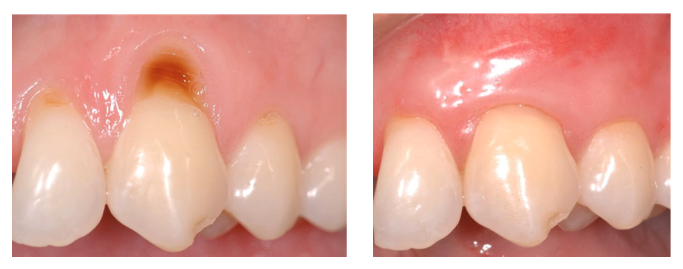

Récession gingivale du collet au niveau de la canine supérieure, résolue par une chirurgie plastique mucogingivale (greffe)